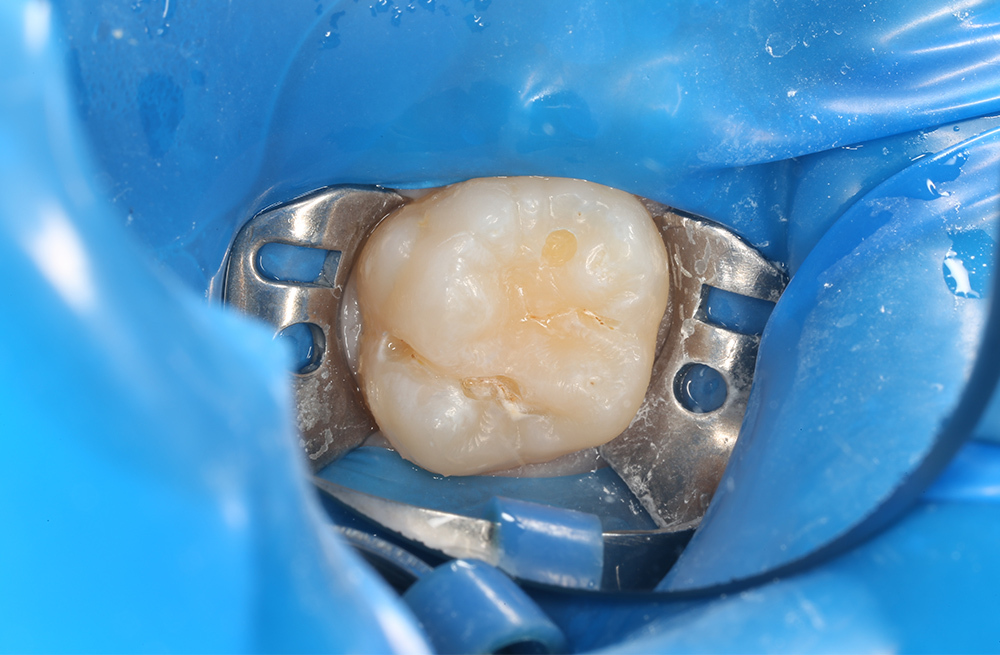

Лечение кариеса на жевательной поверхности постоянного зуба у подростка